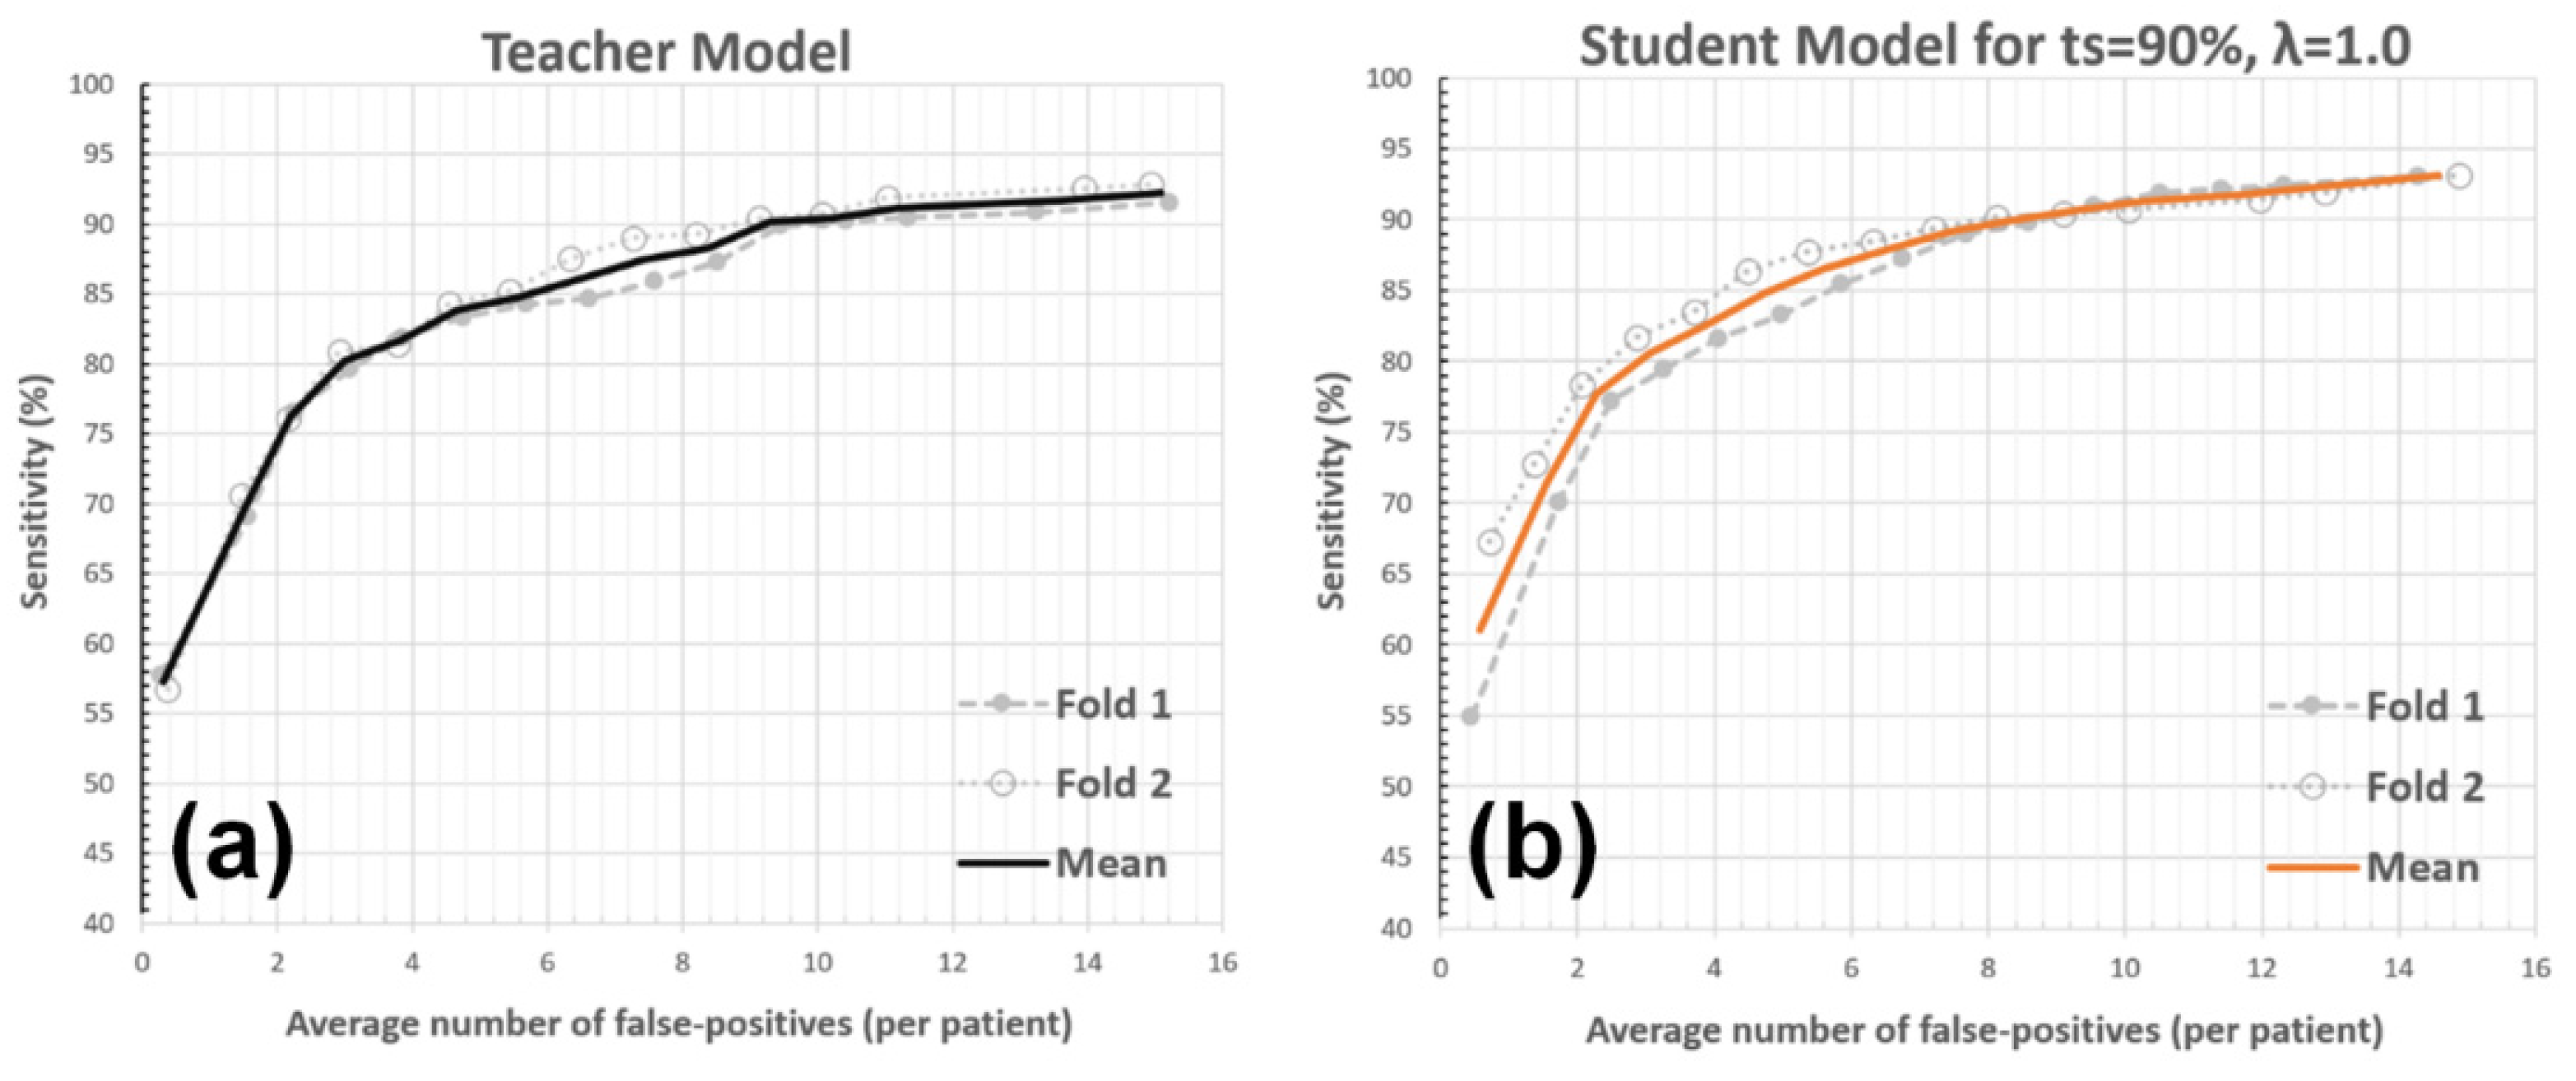

3.1. Validation Study

3.2. Experiments with System Parameters

3.2.1. Teacher Model Sensitivity